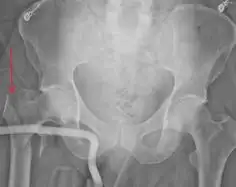

진단 과정

강직인간증후군의 진단은 주로 증상을 바탕으로 이루어지며, 근전도검사와 혈액 검사를 통해 확진합니다.

근전도검사는 근육의 전기적 활동을 측정하여 비정상적인 근육 활동을 감지하고, 혈액 검사는 항체의 존재를 확인하여 자가면역 질환의 증거를 찾습니다.

이러한 검사들은 강직인간증후군의 특징적인 증상과 함께 진단에 중요한 역할을 합니다.